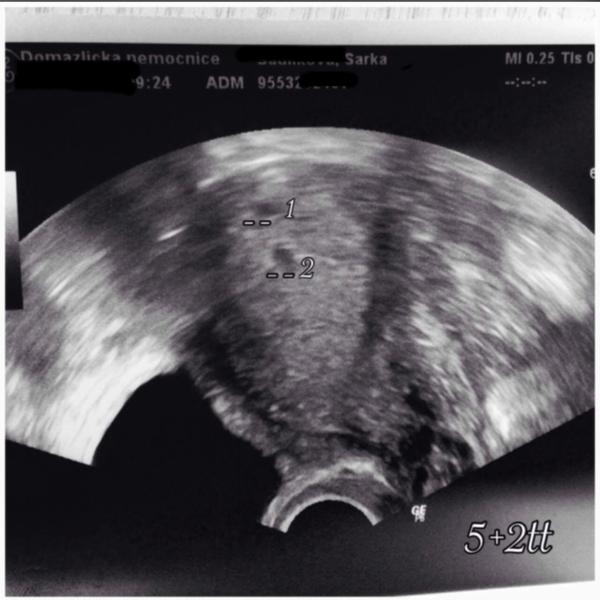

Hlavu vzhůru holky. já měla sp, zt i biochemicke. Některé varianty několikrát. A teď to říkám velmi opatrně. Dnes přesně po dvou letech od doby kdy jsem naposledy otěhotněla a byl z toho zt jsem našla pozitivní tt. A to i přes endometriozu 3-4 stupně. Vím jak to může dopadnout ale věřím že tentokrát to dopadne dobře. Letos mi bude 32 a ditko žádné.